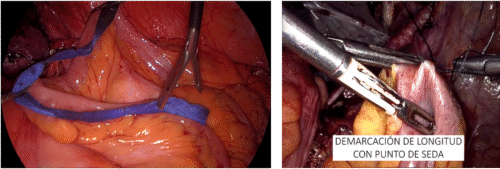

Se seccionan los vasos con tijera fría. En este punto se debe decidir preservar o no la glándula suprarrenal correspondiente o completar la disección del polo superior incluyendo la glándula en la bolsa de Gerota. En el lado izquierdo para preservar la glándula, se debe seccionar la vena renal entre la afluencia de la vena suprarrenal izquierda hacia la vena renal principal y el riñón, ubicar la cápsula renal y abandonar la glándula con la grasa que la rodea. En el lado derecho, posterior a ligar el hilio se debe ubicar la cápsula renal del polo superior dejando la glándula con la porción de grasa del polo superior que la rodea. Se completa la disección de la Gerota en forma roma. Por último se secciona el uréter y los vasos gonadales(19,20). Una vez liberada la pieza, se atrapa en una bolsa de PVC de 15 cm de diámetro y se extirpa por el sitio de Nyhus, previamente preparado (antes del pneumoperitoneo), marcando el sitio con un lápiz indeleble en la piel y disecando la fosa iliaca cuando la cirugía es retroperitoneal. Recomendamos hacer la marcación de este sitio antes de efectuar el pneumoperitoneo ya que, cambia la disposición anatómica con el abdomen insuflado. La ventaja del abordaje retroperitoneal es que se evita la disección de vísceras intraperitoneales. Como desventaja se tiene un campo quirúrgico más reducido.

Realizamos aseo de la cavidad abdominal, si es necesario, con abundante agua bidestilada. Reponemos el riñón en la bolsa de Gerota, suturándola con un punto continuo de material reabsorbible. Se extirpa la bolsa con la lesión integra por un sitio de punción, si el tamaño lo permite o por el sitio de Nyhus. Se completa el procedimiento verificando la ausencia de sangrado en los sitios de punción, común a todas las cirugías. En resumen, nuestra técnica de nefrectomía parcial contempla: resección del tumor por enucleación y reparación de estructuras vasculares o vía urinaria con clips en la superficie del lecho tumoral que no comprometen otras estructuras profundas. La reparación del defecto quirúrgico con puntos superficiales separados de material absorbible sobre un rollo de celulosa oxidada. Con esto necesitamos menor tensión y provocamos menor daño isquémico (técnica de reparación superficial) (Figura 28).